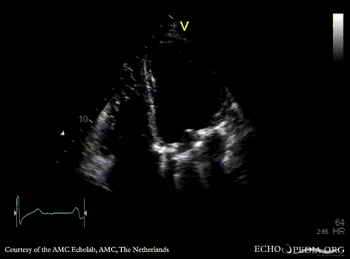

E00598.gif E00599.gif

A4CH A2CH